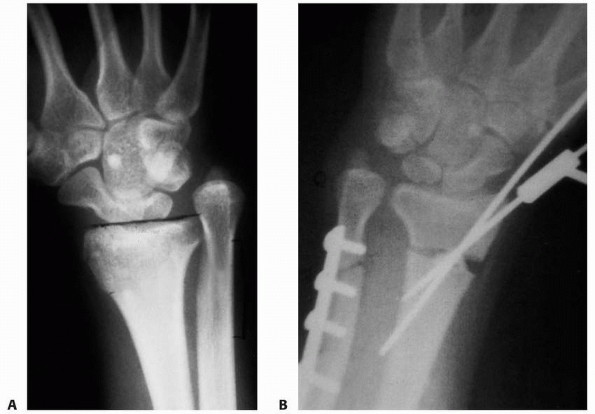

![]() |

|

FIGURE 9-31 A,B. A 10-year-old boy sustained a closed Salter-Harris type I separation of the distal ulnar physis (arrows) combined with a fracture of the distal radial metaphysis. C. An excellent closed reduction was achieved atraumatically. D. Long-term growth arrest of the distal ulna occurred.